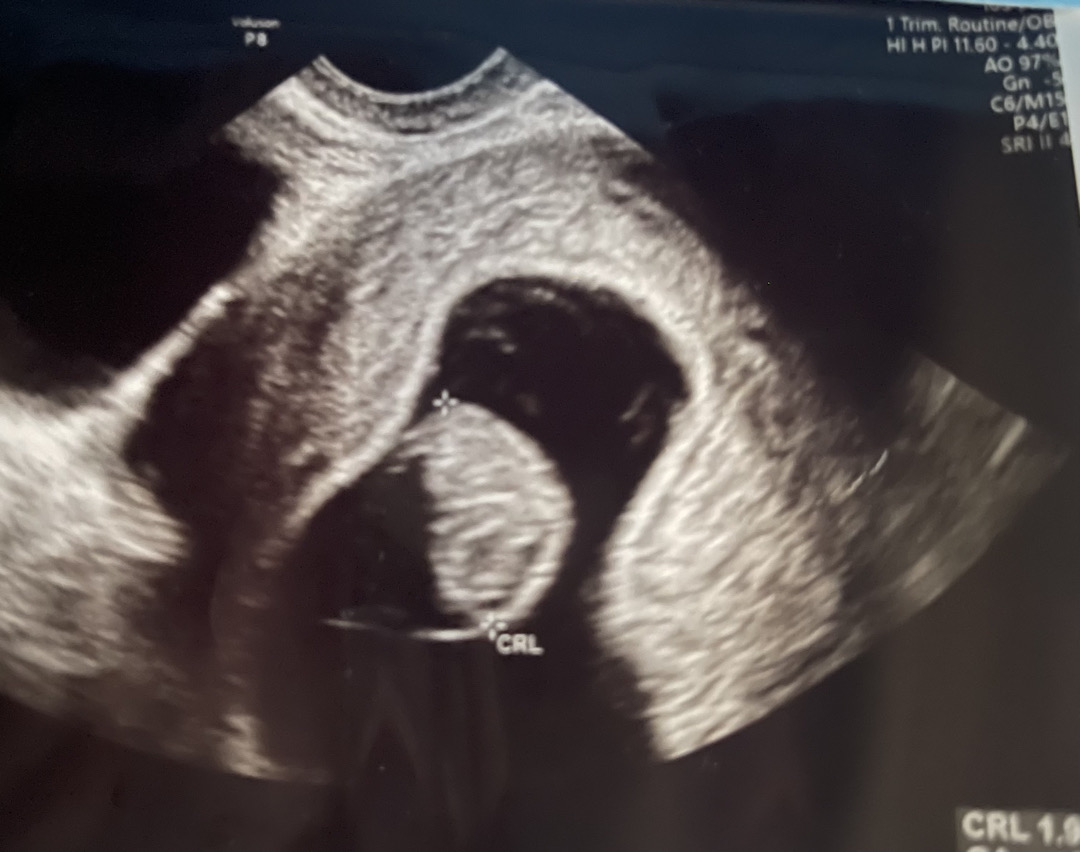

8주차 드디어 촘파 보고왔어요~

아직 8주라서 그런지 젤리곰은 못봤는데 다리랑 팔이랑 슬슬 자라고 있는거 같더라구요. 머리가 위에 있을줄 알았는데, 우리 한방이는 머리가 이미 아래로.. 주수에 맞게 크고있고 1.9cm래요 ㅋㅋㅋ 담당쌤이 블루베리 사이즈라고 하셨는데.. 쪼끄만게 심장도 있어서 반짝이는거 보는데, 기분이 진짜 묘했어요.. 🥹 다음번에는 심장소리도 듣고싶네용 ㅎㅎ 다들 좋은하루 되세요~~💕